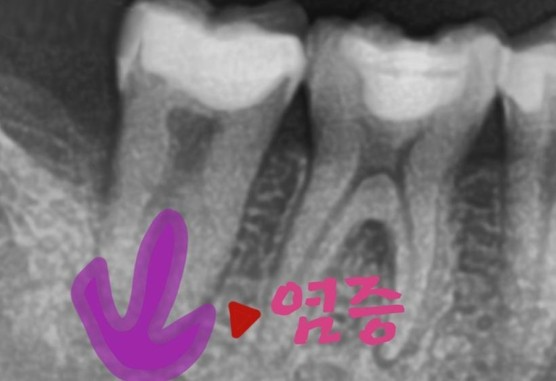

[치아뿌리 주변까지 염증에 이환된 상태]

치아 자체가 흔들리기도 하였고, 발치 가능성을 고지한뒤 신경치료를 시작합니다.